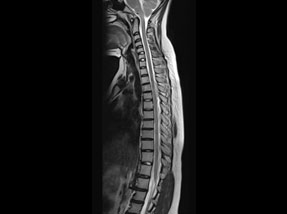

• Pre-SurgeryBefore

• Post SurgeryAfter

Case 1